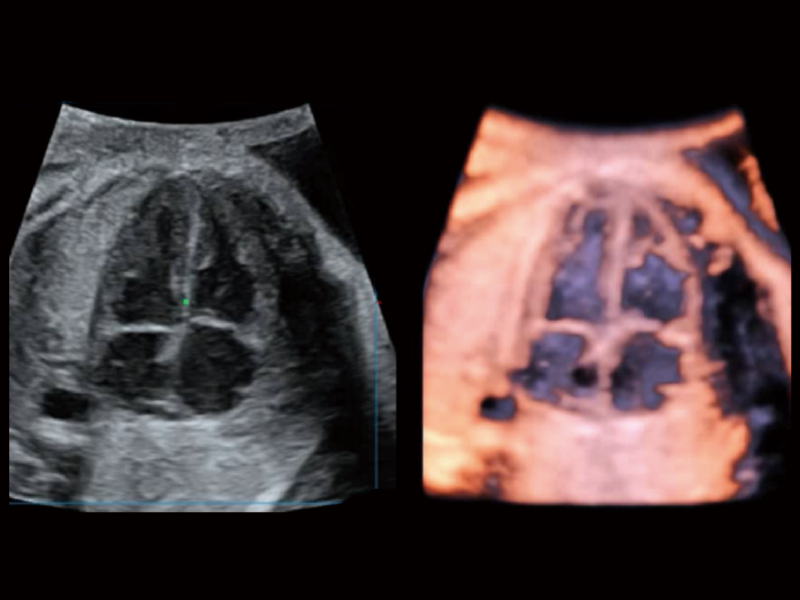

作为开立医疗全新打造的超高端旗舰超声产品,从探头抬起唤醒开启扫查到多维探头发射接收,通过先进的场成像发射、自适应聚合重建等技术,基于RF Data原始射频数据在图像生成、高端功能等方面实现突破,为妇产科、儿科提供全方位临床解决方案。

通过光照模型,使二维血流显示出立体的效果,增加血流的敏感性、成束性,减少外溢。可以和其他不同的血流技术联合使用,融合不同技术的优势。轻松应对微小血管,增强血流的立体效果,提升视觉敏感性。

梦溪®P80以“关爱女性”为基石,提供全方位的解决方案,量身定制以满足女性的健康需求,涵盖妇科、生殖健康检查、产前筛查及产后康复等领域。